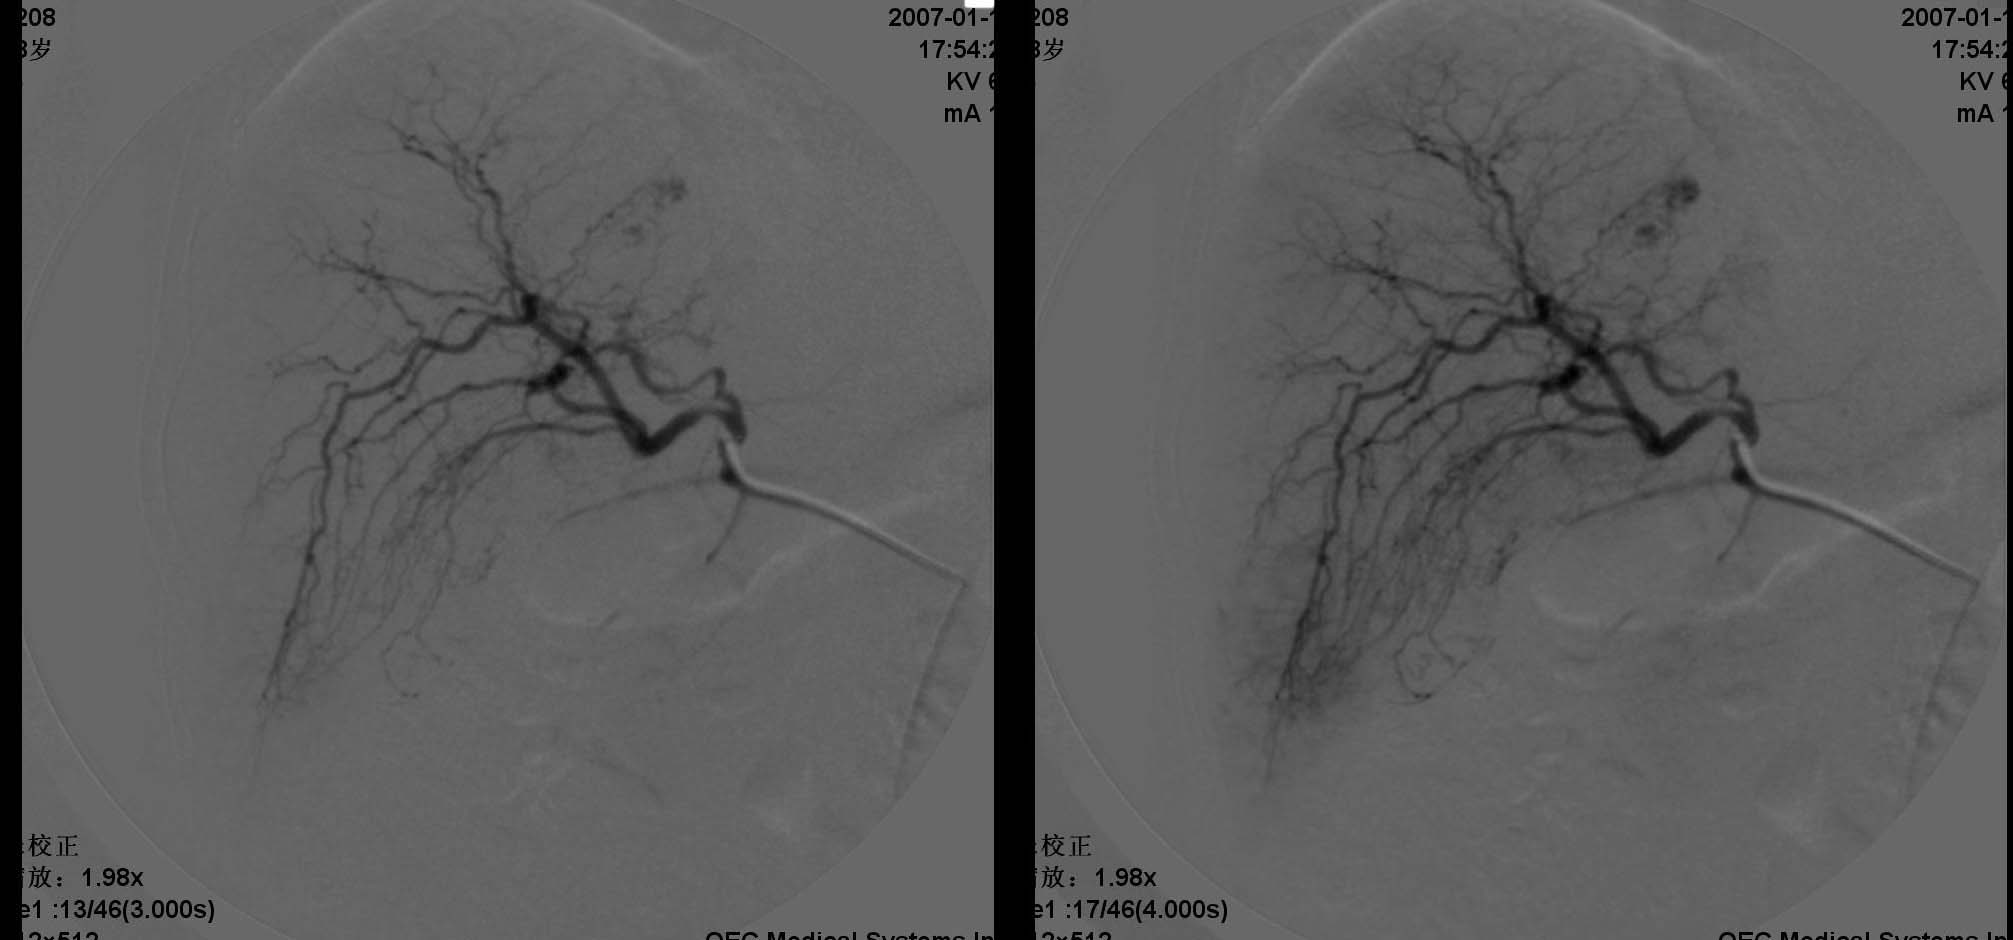

患者男性,38岁,因血便4天入院.查体:神请,颈无抵抗,心肺听诊无异常.腹部平软,肝肋下两指,轻度扣击痛,肠鸣音正常,神经系统无阳性发现.2006年6月份因结肠癌行右半结肠切除术.入院化验阳性结果:癌胚抗原增高.b超发现右肝两处异常,ct显示右肝及脾脏均为多个低密度病灶,肠镜显示降结肠息肉.

动脉期见肝右动脉稍增粗,实质期肝右叶可见两个类圆形染色区,以边缘部为著.脾脏病灶类似.首先考虑转移瘤.